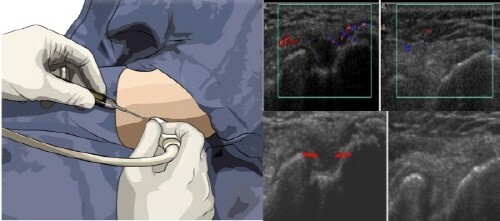

수술 방법은 고해상도 초음파와 0.5mm 정도에 외과용 Micro-Needle로 진행된다. 초음파를 통해 염증에 발현부위 그리고 주변조직과 유착 정도와 분포 형태, 힘줄 손상에 정도를 파악한 뒤 유리술이 필요한 부위에 타겟점을 형성한 뒤 이곳에 Micro-Needle을 삽입해 실시간으로 관찰하며 유리술을 시행한다.

유리술이 끝나고 나면 초음파 도플러 기능을 통해 혈류 흐름을 관찰한다. 이 과정이 중요한 이유는 해부학적으로 외·내상과 부위는 혈류공급이 제한적인 저혈구간으로 수술 후 증상 호전이 없거나 재발을 발생시키는 원인이다.